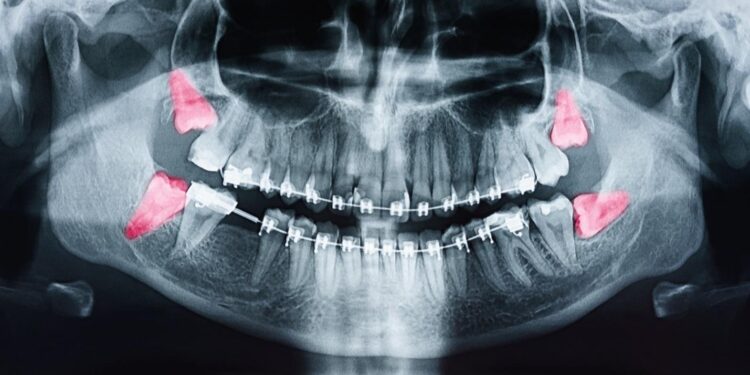

If you suspect you have a wisdom tooth infection based on these symptoms, it’s essential to seek professional dental care. A dentist will examine the affected area, possibly taking an X-ray to assess the extent of the infection. Treatment may involve antibiotics, pain management, or in severe cases, extraction of the affected tooth.